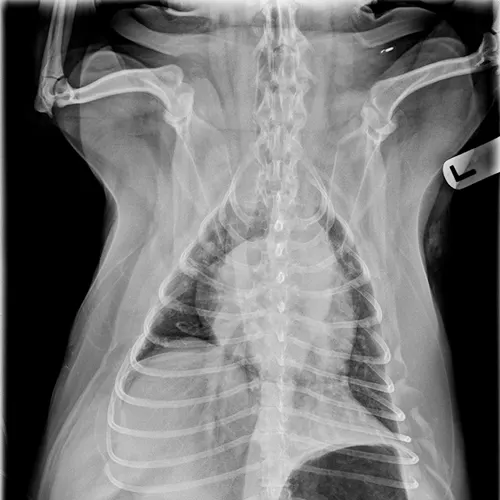

Pulmonary neoplasia may, on occasion, have a more diffuse nature. This is common with pulmonary lymphoma40 and is sometimes seen with carcinoma (author experience). Pulmonary lymphoma can have a rapid clinical course and mimic acute disorders. A diffuse, unstructured interstitial pattern is typically appreciated. Additionally, bronchointerstitial, alveolar, and nodular patterns may be observed (Figure 7).40

FIGURE 7

(A) Pulmonary lymphoma with a diffuse, patchy bronchointerstitial pattern confirmed on bronchoalveolar lavage and peripheral lymph node aspiration. (B) Pulmonary carcinoma with a diffuse, severe bronchointerstitial pattern confirmed on bronchoalveolar lavage and postmortem examination. Note: Pulmonary and hilar lymphadenopathy are not always present.